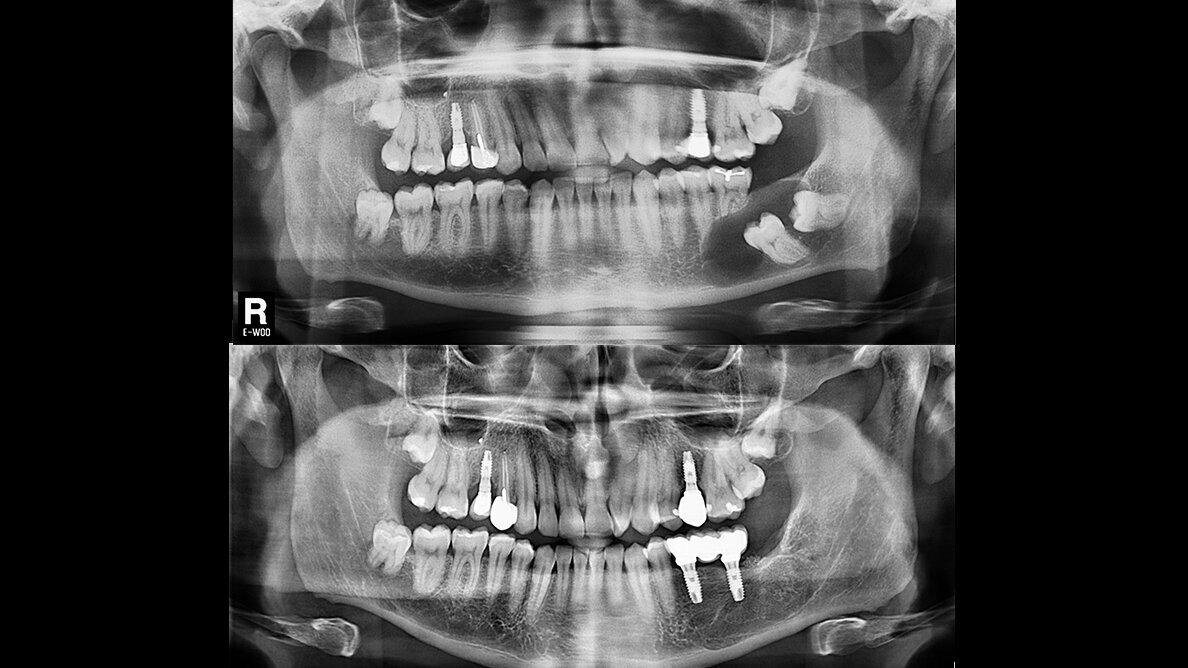

Se realizó el control radiográfico de la zona tratada durante 12 meses. El paciente fue evaluado de forma clínica y radiológica (Fig. 10).

Figura 10. Evolución postoperatoria. El paciente acude a consulta para control radiográfico de la zona intervenida. A) La ortopantomografía evidencia el área menos radiotransparente y sugiere una neoformación ósea de la cavidad quística a los 8 meses. B) A los 12 meses se observa un tejido más radiopaco y con trabeculado óseo, compatible con hueso en fase de maduración.

Se planificó la colocación de dos implantes mediante TCHC. Tras la evaluación tridimensional se observó un defecto óseo residual en distal del implante planificado en posición 3.7 (Fig. 11).

Figura 11. Planificación de implantes. Evaluación intraoral de la zona tratada. A) Se evalúa las necesidades protésicas y calidad de los tejidos blandos. B) En un vista oclusal, se observa los tejidos blandos saludables y presencia de mucosa queratinizada. C) Se realiza una TCHC y se planifica la colocación de dos implantes dentales en posición 3.5 y 3.7.

Dos implantes de 4.7 mm de diámetro y 11 mm de longitud fueron instalados (Phibo TSA®, Phibo Dental Solutions, Barcelona, Spain). El defecto residual en distal de 3.7 fue regenerado de forma simultánea con ß-fosfato tricálcico (KeraOs®, Keramat, A Coruña, Spain) (Fig. 12).

Figura 12. Cirugía de implantes. A) Despegamiento de colgajo a espesor total. B) Tras la preparación del lecho implantario se instalan dos implantes dentales en posición 3.5 y 3.7. C) Colocación de tapas de cierre. D) Se coloca un injerto particulado aloplástico para regenerar el defecto óseo distal del implante en posición 3.7. E) Cierre del colgajo con puntos interrumpidos con seda no reabsorbible.

El caso fue evaluado a los 24 meses de carga funcional. El examen radiológico mostró un adecuado nivel del hueso marginal respecto al día de instalación de los implantes, así como la neoformación de la zona asociada a la patología quística (Fig. 15).

Figura 15. Ortopantomografía. A) Día de la colocación de implantes. B) A los 24 meses tras la carga funcional de los implantes.